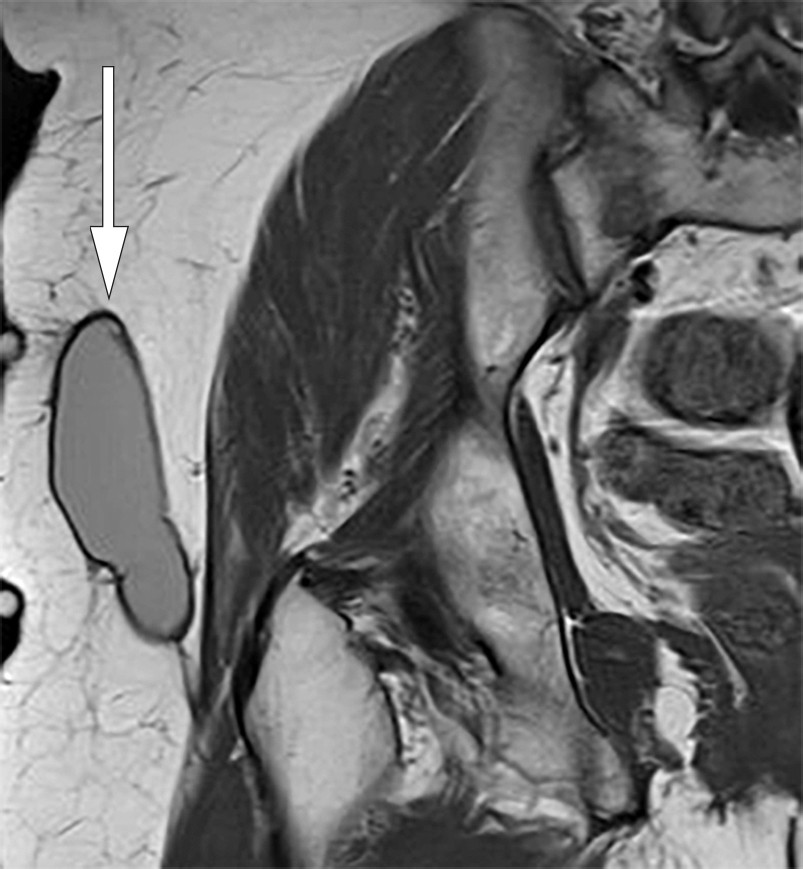

Figure 1 Coronal T1-weighted MRI of right hip. Well-defined, elongated, lenticular structure with homogeneous intermediate…

Figure 1 Coronal T1-weighted MRI of right hip. Well-defined, elongated, lenticular structure with homogeneous intermediate signal located over the deep fascia.

Eleven months after the trauma, the patient experienced another recurrence, and pelvic MRI revealed an unchanged subcutaneous locule. The radiologist suspected a Morel-Lavallée lesion (Figure 1). It was decided to perform an elective open excision of the locule, including the capsule, with primary suturing in the operating theatre. One week after the excision, the patient experienced another recurrence. A further aspiration was performed and compression attempted in the outpatient clinic, but without success.